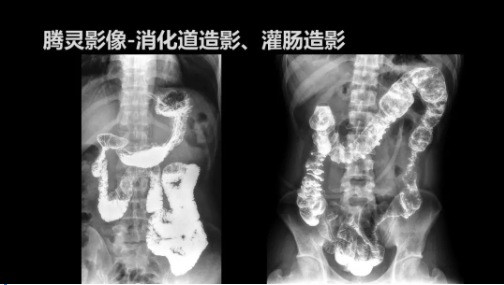

“騰靈”是安健科技的第四代動(dòng)態(tài)DR產(chǎn)品,可實(shí)現(xiàn)全科室應(yīng)用。如各類常規(guī)的X線檢查、消化道檢查、骨科檢查、婦科、兒科檢查等。此外,安健科技為“騰靈”在真正意義上實(shí)現(xiàn)多科室、多功能診斷進(jìn)行了多項(xiàng)針對(duì)性設(shè)計(jì)。

此外,“騰靈”為了能夠幫助醫(yī)生更快速、有效的定位病灶,還增加了多項(xiàng)精準(zhǔn)診斷保障功能,如支持動(dòng)態(tài)觀察診斷,實(shí)時(shí)高清點(diǎn)片等。“騰靈”透視切換高清點(diǎn)片曝光,捕捉關(guān)鍵病灶診斷僅需0.8s,同時(shí)還支持圖像局部放大,醫(yī)生可自由切換15’12’和9’三種放大模式,另外,“騰靈”還支持視頻保存、回放功能,幫助醫(yī)生在檢查結(jié)束后通過(guò)回放查看細(xì)節(jié),為醫(yī)生的診斷增加信心。